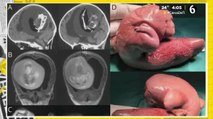

El sorprendente caso de una mujer de 80 años con un feto momificado en su interior asombra a Durango y al mundo.

El extraño caso de la mujer con "bebé de piedra" en su interior

Hallan un feto calcificado hace 40 años en el vientre de una anciana

Una mujer brasileña con un feto calcificado desde hace 30 años muere en una operación